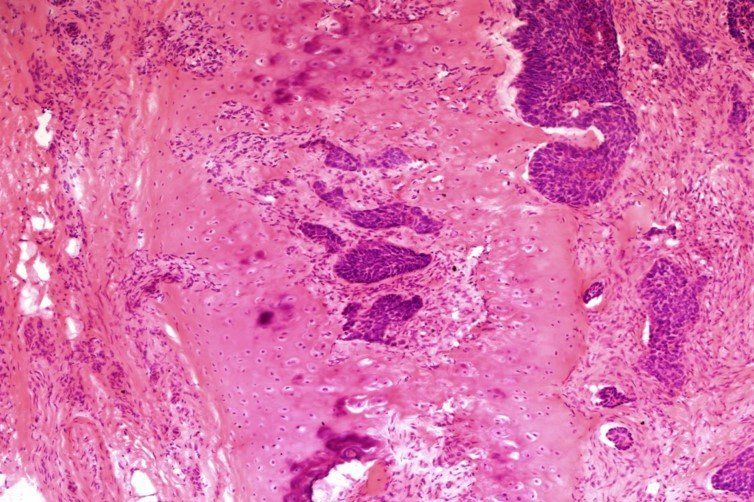

H E - schemat Mohsa

Oto slajd H E przedstawiający naciek raka podstawnokomórkowego na chrząstkę z tkanki pobranej z grzbietu nosa. Punkty odjęto za: zbyt intensywne wiązanie eozyny, ślady po nożu, fałdy i bruzdy. Ten slajd uzyskał ocenę 7/10.